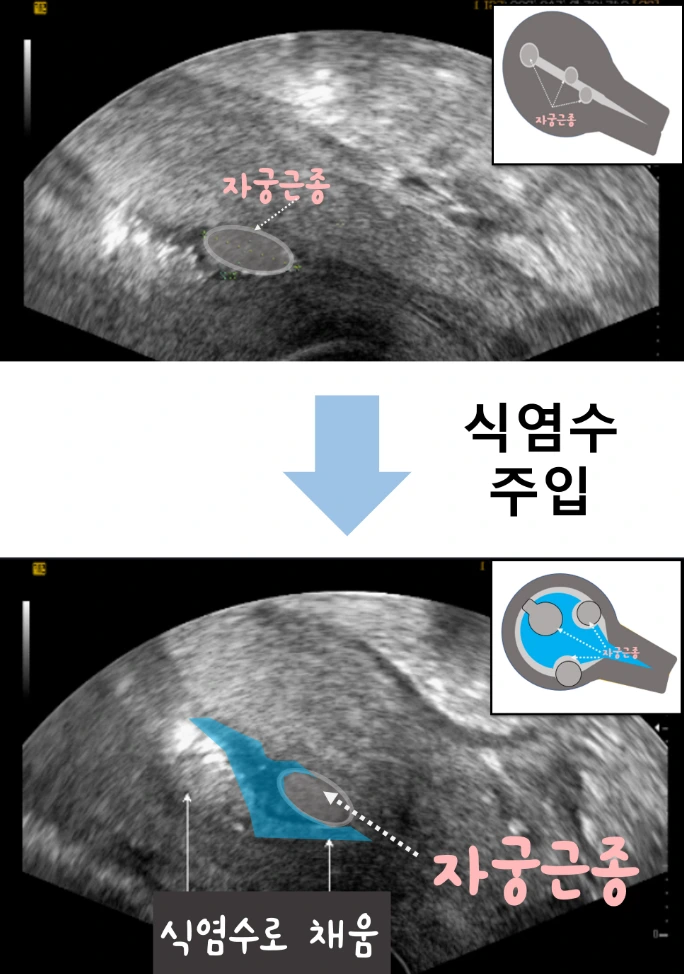

신체의 체액과 유사한 식염수(Saline)를 자궁 내부 공간에 주입해서 초음파 영상을 보는 방법입니다. 우리가 흔히 보는 자궁 도식화와 달리 근종이 자궁내막에 위치한 경우, 일반 초음파 검사로 정확하게 평가하기 어렵습니다. 하지만 자궁 안쪽 공간에 식염수를 채워 넣게 되면, 자궁근종의 개수, 위치, 양상이 더 명확해지고 식염수로 인해 초음파 영상이 더욱더 선명하게 보이기 때문에 일반 초음파 검사에 비해 정확한 평가에 도움이 됩니다.

생리식염수란, 인간 신체의 체액을 0.9% NaCl(염화나트륨) 용액으로 가정하여, 이와 농도를 동일하게 조정하여 제조한 액체로 인체에 무해합니다.

그리고 자궁근종의 뿌리(stalk) 위치까지 파악할 수 있어서 시술로 제거하는 데 도움이 될 수 있습니다. 마취 없이도 검사를 진행할 수 있으나 시술의 불편함으로 인해서 수면 마취하에서 시행하기도 합니다. 참고로, 마취를 하지 않았을 때의 불편함은 '질초음파+α'입니다. (마취 여부는 병원 및 담당 선생님마다 다를 수 있습니다.)

식염수를 채워 넣으면 공간에 식염수가 공간을 확보해주어서 근종이 자궁 안쪽 공간에서 어디에 위치하는지 쉽게 평가할 수 있습니다.